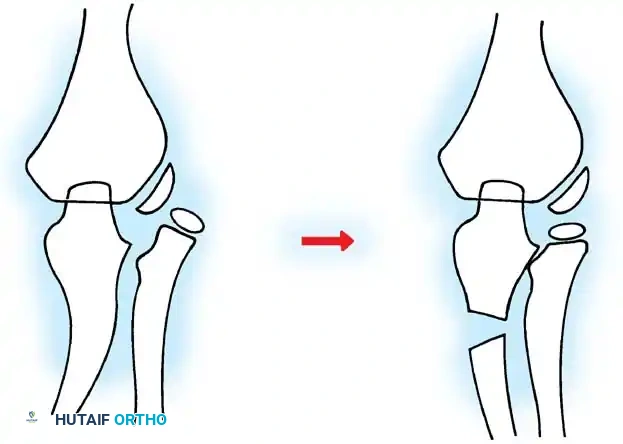

Fractures can present as angulated, translocated (shifted), or totally displaced. In the context of an elbow dislocation, the proximal fragment may become loose within the joint space or trapped, acting as a mechanical block to reduction.

Fig. 33-40 Examples of angulation, translocation, and total displacement of radial neck fractures.